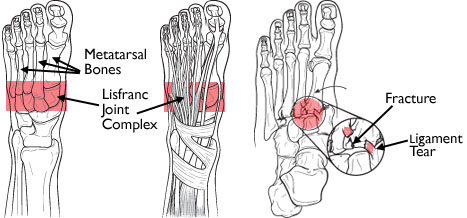

AnatomyThe midfoot is the middle region of the foot, where a cluster of small bones forms an arch on the top of the foot. From this cluster, five long bones (metatarsals) extend to the toes. The bones are held in place by connective tissues (ligaments) that stretch both across and down the foot. However, there is no connective tissue holding the first metatarsal to the second metatarsal. A twisting fall can break or shift (dislocate) these bones out of place.

The Lisfranc joint complex has a specialized bony and ligamentous structure, providing stability to this joint.

The Lisfranc joint complex includes the bones and ligaments that connect the midfoot and forefoot. Lisfranc injuries include ligament strains and tears, as well as fractures and dislocations of bone (far right).